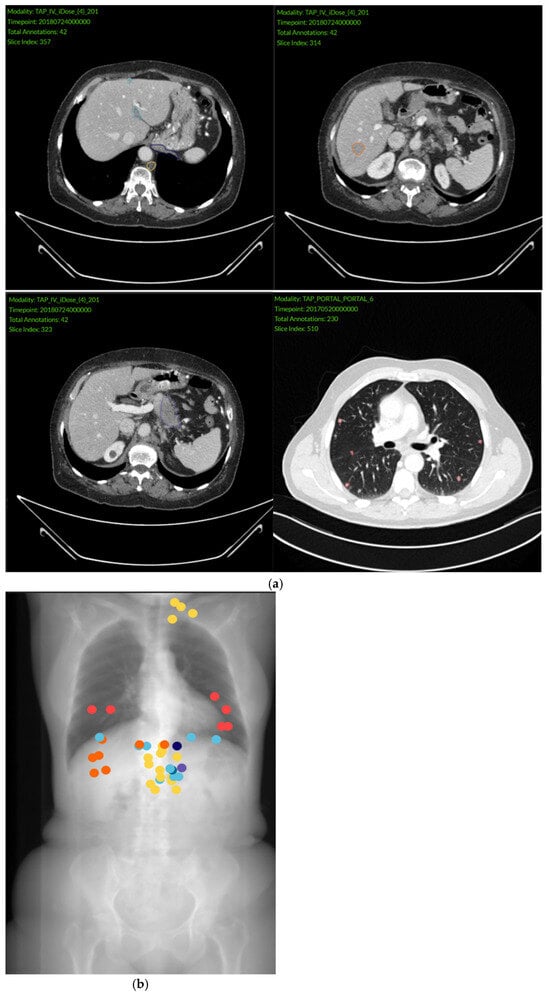

Background: Total tumor volume (TTV), derived from imaging data, has emerged as a potential prognostic biomarker in various cancers. This study aimed to evaluate the impact of TTV on outcomes in advanced pancreatic ductal adenocarcinoma (PDAC) and to validate a survival prediction model combining TTV with baseline clinico-biological markers. Materials and Methods: We conducted a retrospective analysis of 150 patients with locally advanced or metastatic PDAC treated with first-line FOLFIRINOX from 2010 to 2021. TTV was calculated by manually segmenting all visible lesions on baseline CT scans. Progression-free survival (PFS) and overall survival (OS) were the primary endpoints. A cut-off value for TTV predicting 6-month PFS was determined in 140 patients using AUC and Youden’s Index and then applied to OS analysis. A multivariate Cox regression model incorporating TTV, CA 19-9, and neutrophil-to-lymphocyte ratio (NLR) was developed in 94 patients to establish a survival risk score. Results: 12,028 lesions were annotated. OS was slightly but significantly different between TTV above and below the median value of 69.60 cm3 (12.4 vs. 13.5 months, p = 0.0269). A cut-off of 400 cm3 distinguished two groups: patients with TTV > 400 cm3 had significantly shorter OS (9.4 months) compared to those with TTV ≤ 400 cm3 (13.0 months, p = 0.0056). A similar trend was observed for PFS, though not statistically significant (7.4 months for TTV > 400 cm3 vs. 8.2 months for TTV ≤ 400 cm3, p = 0.0735). The combined model achieved a mean c-index of 0.62 for PFS and 0.64 for OS. Based on the risk score, high-risk patients had significantly worse median PFS (5.5 vs. 9.2 months, p = 0.0008) and median OS (7.2 vs. 13.5 months, p < 0.0001). Conclusions: TTV is a valuable prognostic marker in advanced PDAC. A model integrating TTV with biological markers enhances survival prediction and supports risk stratification in clinical practice.